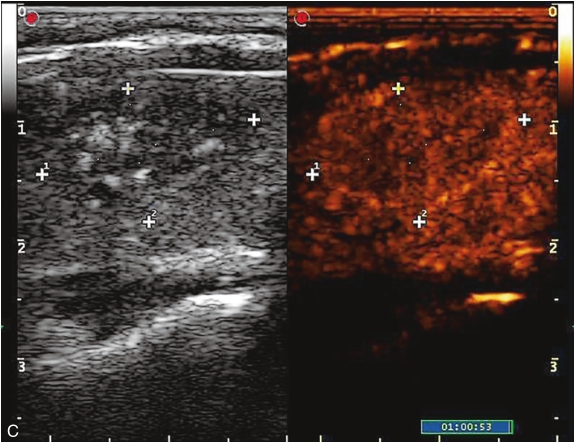

注射造影剂后,10s病灶早于周围甲状腺组织开始增强,呈不均匀高增强,13s达峰值,19s开始减退,至增强晚期病灶减退呈不均匀稍低增强。见图1-9-2、ER1-9-1。

甲状腺髓样癌常见超声造影表现为低增强、不均匀低增强及向心性低增强。但若病灶内血管分化较多,也可能出现高增强表现。

图1-9-2 甲状腺髓样癌造影图像

A.造影后10s;B.造影后13s;C.造影后19s;D.增强晚期